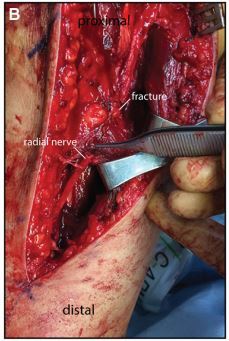

9

Q

How will you manage an open Holstein-Lewis fracture?

A

1. Surgically.

2. Begin with thorough/adequate wound debridement and open reduction and internal fixation of the humerus fracture.

3. Radial nerve exploration.

• If lacerated, performed debridement of damaged ends of nerve and nerve grafting.

• If in continuity, leave it alone, expectant management as neurpraxia injury usually with eventual spintaneous recovery (60-90%).

10

When will you explore radial nerve in radial nerve palsy following fracture of humerus?

Acute setting

1. Open fracture of humerus- WD and ORIF planned, can include exploration of nerve.

2. Vascular injury present.

3. Penetrating injury present

Delayed setting

by 6 months, when no signs of nerve recovery by clinical or electrodiagnostic assessments.

11

Nerve repair

During wound debridement and ORIF of an open humerus fracture, you encountered this. How will you manage this?

Intra-operative finding is of a transected radial nerve following open fracture of the humerus in context of high-energy motorvehicle accident. (Have to highlight that high energy injury, has high risk of neurovascular injury, also need TRO vascular injury which is more important for limb salvage)

After performing thorough wound debridement and plating of the humerus fracture (if vascular injury present, neuroraphy is after), I will proceed to addressing the transected radial nerve.

Using loupe or microscopic magnification, I will identify the proximal and distal portions of the transected radial nerve, using Jewellers forceps to handle these portions with care by only manipulating/holding the epineural layer.

• perform neurolysis to mobilise nerve ends about 1-2 cm at either end (to gain lenght to minimise tension on the nerve repair) whilst preserving the common sheath of the neurovascular bundle (to maintain nerve vascularity)

• Nerve fascicle ends are trimmed untill clean and pouting.

• Epineurium layer is identified circumferentially, both ends of fascicular bundles are aligned to match by way of blood vessels markings in epineurium.

• Using a background to aid visualisation.

• If resultant gap does not allow tension-free repair (after elbow joint positioning done, and only direct end-to-end possible with elbow flexed), you CANNOT perform end-to-end repair. Proceed with nerve transfer using autologous donor nerves - sural, medial/lateral antebrachial cutaneous.

** Primary repair can be done with elbow in flexion but this position is maintained for 3 weeks after surgery and subequently elbow is extended 30 deg/week untill full extension is obtained.

• Suture chosen is monofilament and has a atraumatic needle (round bodied) to minimise trauma to the nerve ends. Suture size 8/0 in arm (9/0 in fingers).

• Place 2 simple sutures 180 degrees from one another first, leaving one tail of each suture longer to stabilise the nerve during repair.

• Anterior repair: place 3-4 sutures in simple interrupted technique, on anterior face/wall to approximate only the epineurium later. Avoid penetrating the fascicles.

• Posterior repair: complete posterior face/wall with 3-4, in simple interrupted technique to approximate only the epineurium later. Avoid penetrating the fascicles.

• Cut long tails short.

• Irrigate wound.

• Closure of wound.

• Immobilise the extremity with above elbow with distal extension with cock up splint (can later order for dynamic splinting):- place elbow in 90 degrees of flexion and wrist is POSI.